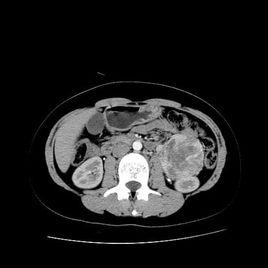

腹膜繼發腫瘤的共同影像表現有腹膜增厚、網膜結節或網膜餅形成、腹水等,但4種腹膜繼發性腫瘤的治療及預後不一。PC最常見,有原發瘤病史者出現上述影像表現應首先考慮該病;腹水以低密度為主時,應考慮到假性黏液瘤及黏液性癌腹膜轉移;出現脾大、淋巴結腫大、腸系膜腫塊時,應考慮到腹膜淋巴瘤;PS極為少見,其轉移結節常邊界清楚,一般不伴腹水及淋巴結腫大。腹膜繼發腫瘤還應與腹膜原發腫瘤、腹膜感染性疾病相鑑別。

腹膜腫瘤可進行超聲、CT、MRI等影像檢查。超聲檢查由於其方便、無創等特點而成為腹膜腫瘤性病變有效的診斷手段之一,可顯示不明原因腹水患者腹膜回聲、形態、厚度情況,行超聲引導下腹膜穿刺活檢能明確診斷。腹水在超聲診斷中起著重要的作用,除了提供良好的透聲能使腹膜的各層清晰顯示以外,亦能起到提示性診斷的作用。